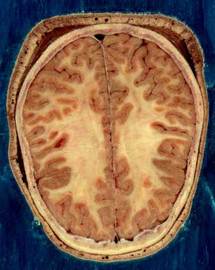

ويأمل علماء مدينة يوليش الألمانية في أن يستطيعوا من خلال هذا الجهاز رصد الأمراض التي تصيب المخ مثل الزهايمر والعته بشكل مبكر وذلك لاتخاذ الإجراءات الطبية اللازمة في الوقت المناسب.

وأعلن مركز أبحاث يوليش اليوم الثلاثاء أن الجهاز يقدم أيضا صورة للهيكل النسيجي للمخ وللعمليات الكيميائية الحيوية به حيث أن القصور المرضي يؤثر بشكل واضح على هذا الهيكل والعمليات الكيميائية الحيوية مما يتيح للعلماء رصد هذا القصور من خلال معرفة التغيرات التي طرأت عليهما.

غير أن المركز أكد في الوقت نفسه أن تحسن فرص التشخيص من خلال هذا الجهاز الجديد لا يعني بداهة تحسن الفرص العلاجية وأن الأمر ربما استغرق سنوات حتى يطور الباحثون طرقا علاجية جديدة اعتمادا على هذه التقنية المتطورة التي يقدمها الجهاز. ومن المقرر أن يبدأ الجهاز في العمل رسميا غدا الأربعاء.